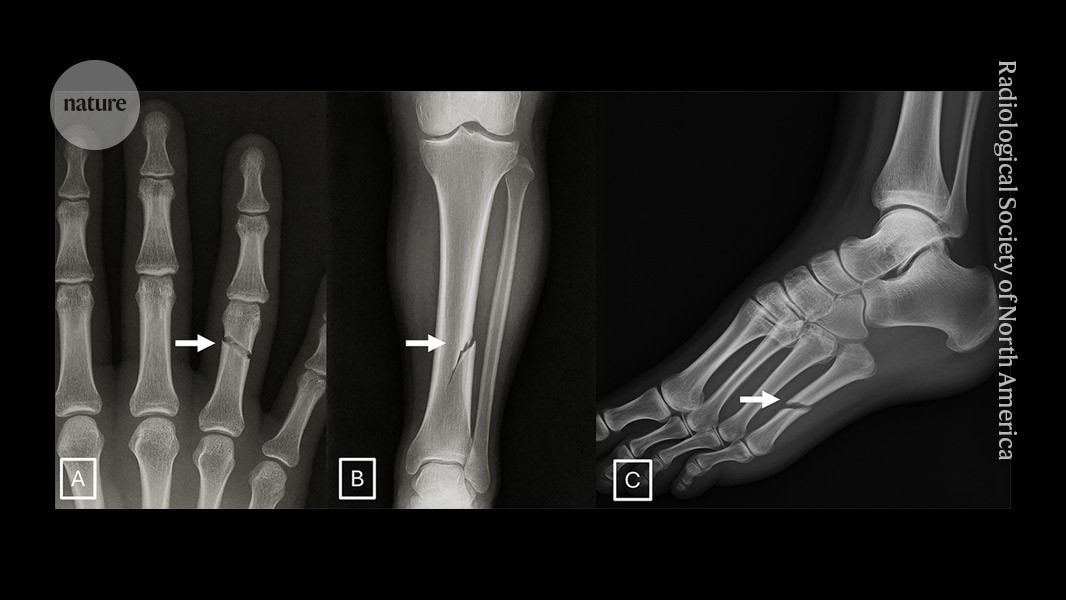

These medical X-rays are all deepfakes — and they fool even radiologists

These medical X-rays are all deepfakes — and they fool even radiologists (current)